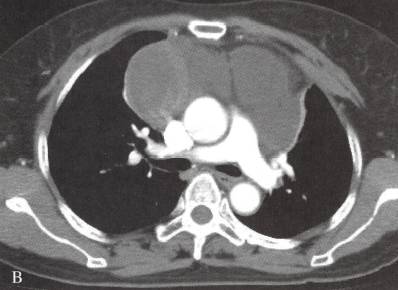

图2多房胸腺囊肿

女性,56岁,胸痛2周。A, B. CT示前纵隔肿物,大部分为囊性,壁厚,有分隔;右侧部分为实性,不均匀环形强化。术后病理为胸腺囊肿,囊壁内见炎细胞浸润、胆固醇结晶,伴出血、退变及坏死